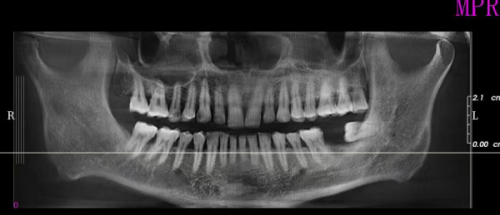

患者的口腔状况也会对手术时长产生影响。如果患者的牙槽骨条件较好,骨量充足,手术操作会相对顺利,时间也会较短。相反,如果牙槽骨存在骨量不足的情况,可能需要精良行骨增量手术,这就会增加手术的复杂性和时间。此外,患者的口腔是否存在炎症等问题,也会影响手术的进程。

首先是种植体植入阶段,也就是前面提到的手术过程,完成后种植体需要在牙槽骨内与骨组织形成骨结合。这个过程通常需要3 - 6个月的时间,具体时间因人而异。在骨结合期间,患者需要等待种植体稳定地固定在牙槽骨中,就像大树扎根一样。

手术前,患者需要进行口腔全方面检查。这包括口腔X光片、CT等检查,医生可以通过这些检查了解患者的牙槽骨情况、牙齿状况以及口腔内是否存在炎症等问题。只有在确定患者的口腔条件适合种植牙手术的情况下,才能进行手术。如果检查发现有问题,可能需要精良行相应的治疗,这就会增加整个治疗的时间。